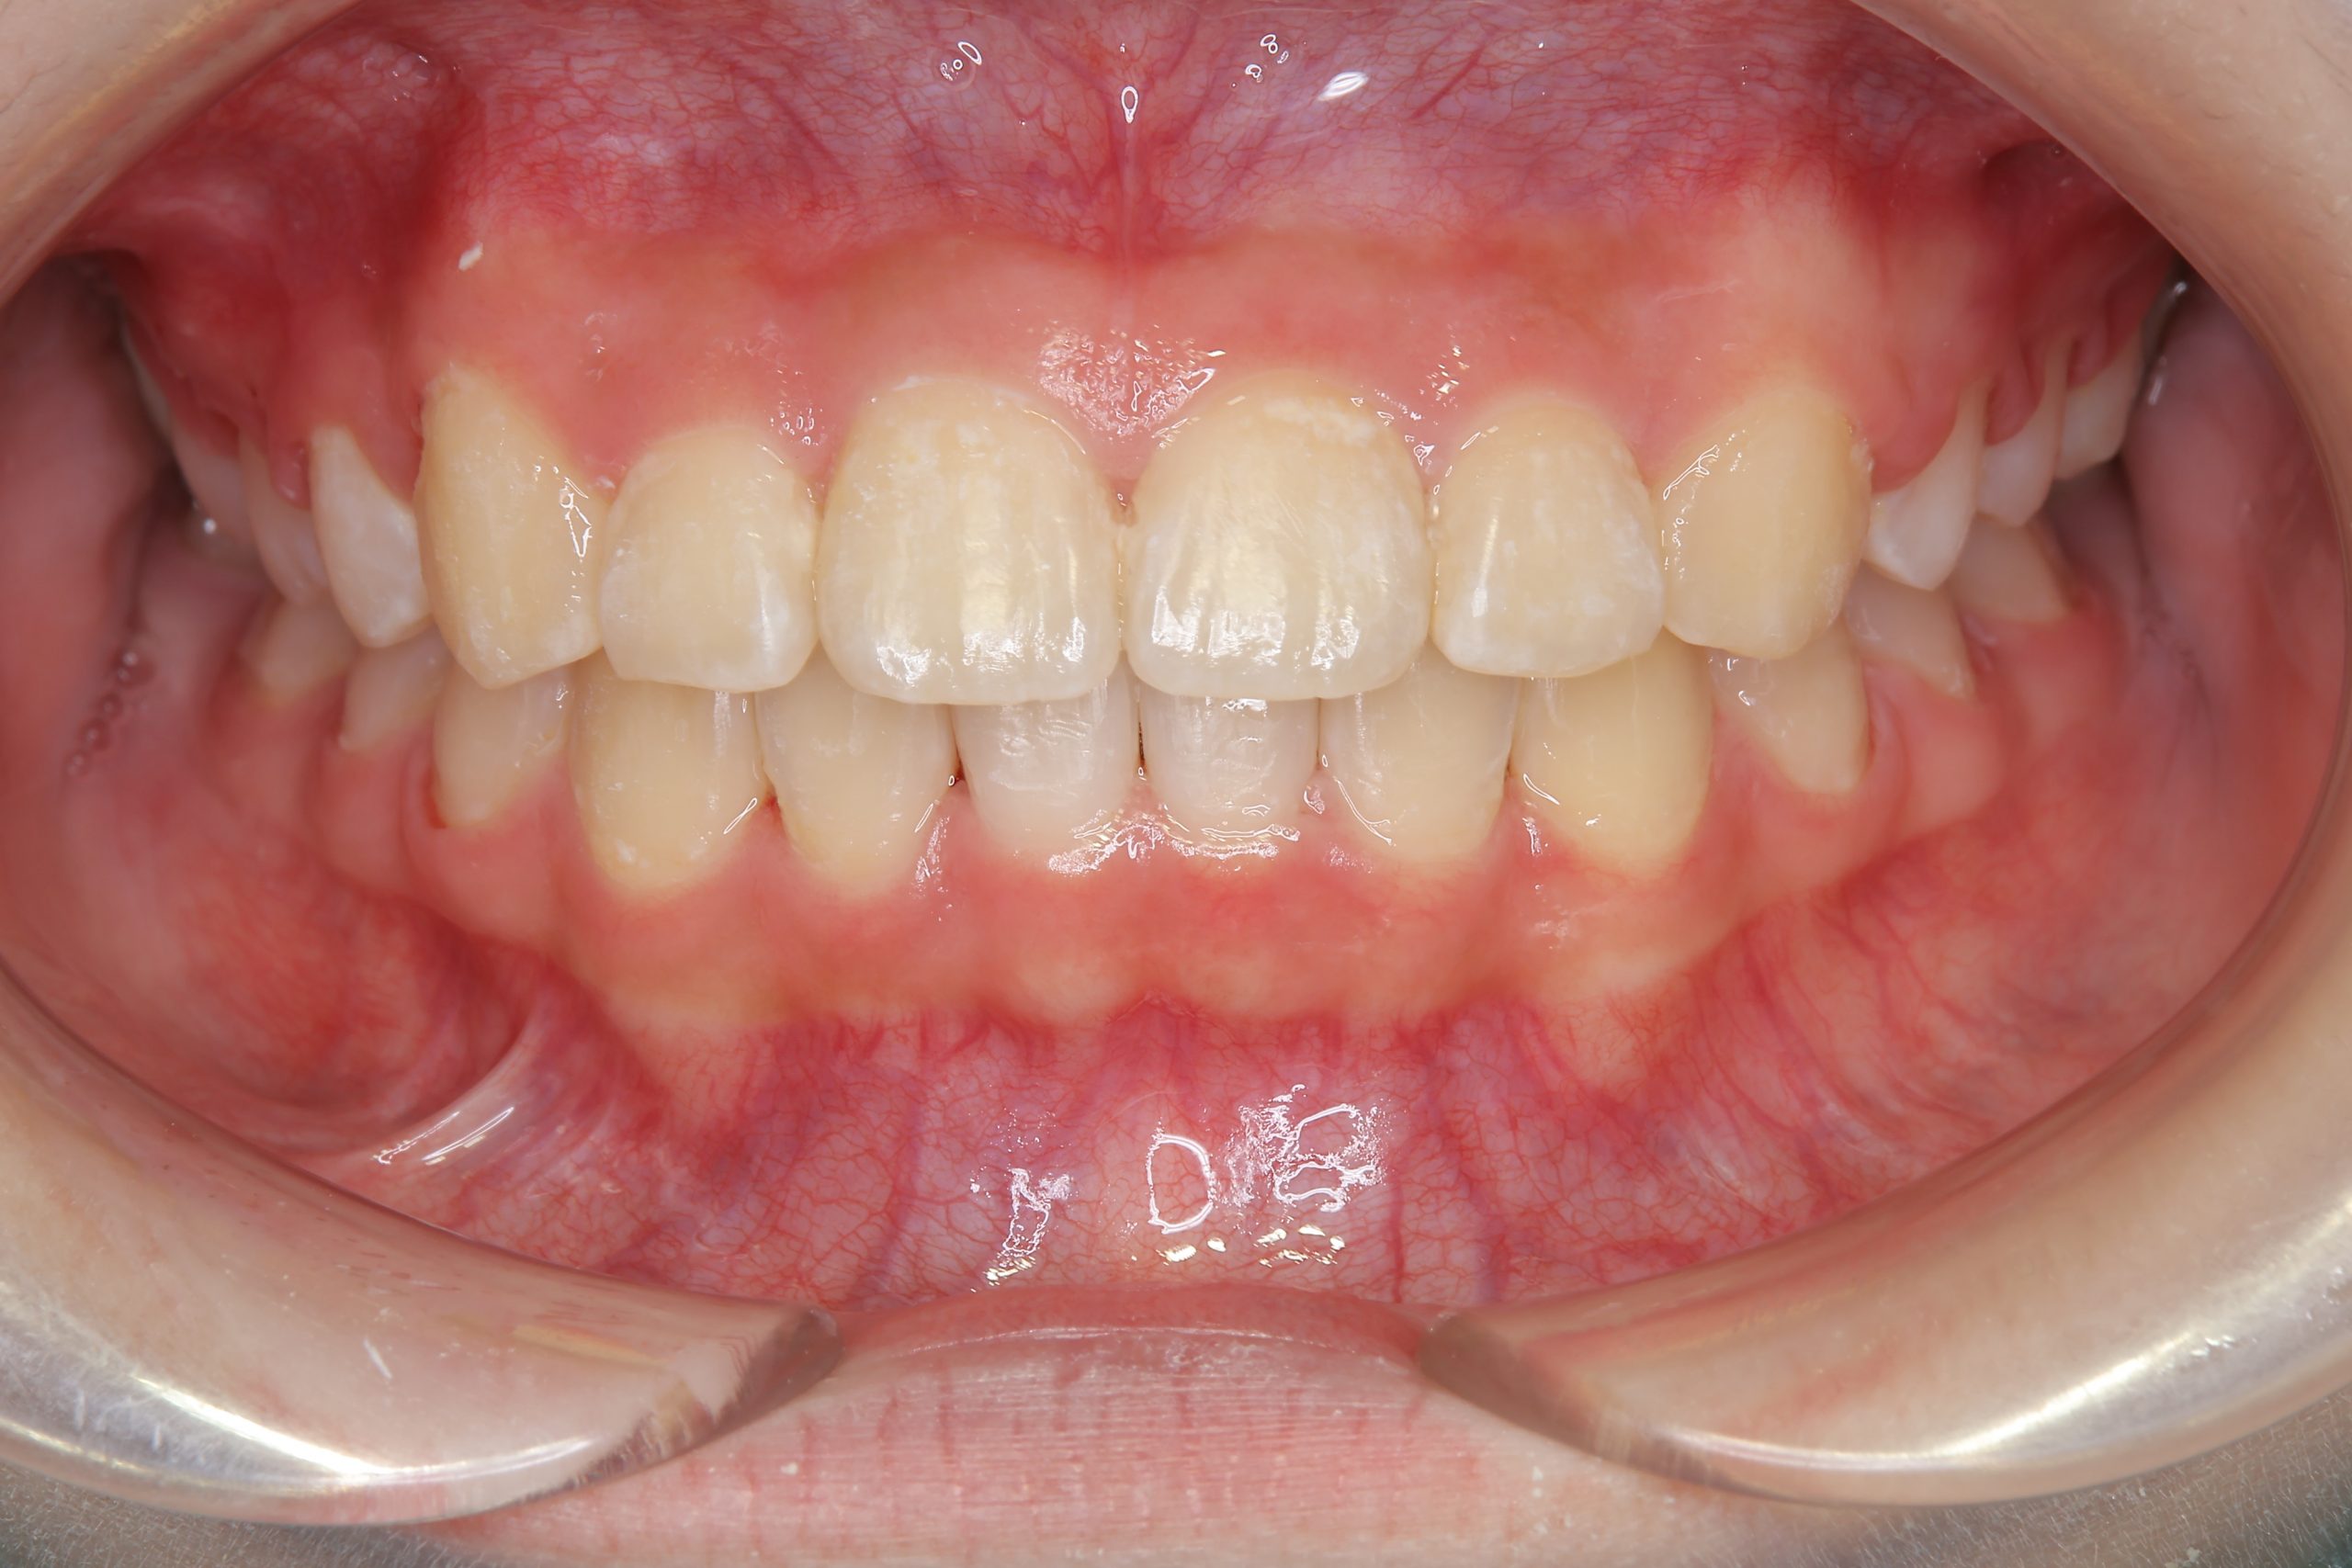

アフター

全顎ワイヤー矯正 症例_805

主訴 中心から前歯がずれている

施術内容 成人矯正1期治療

治癒期間 1年3か月間

費用 954,800円(税込)